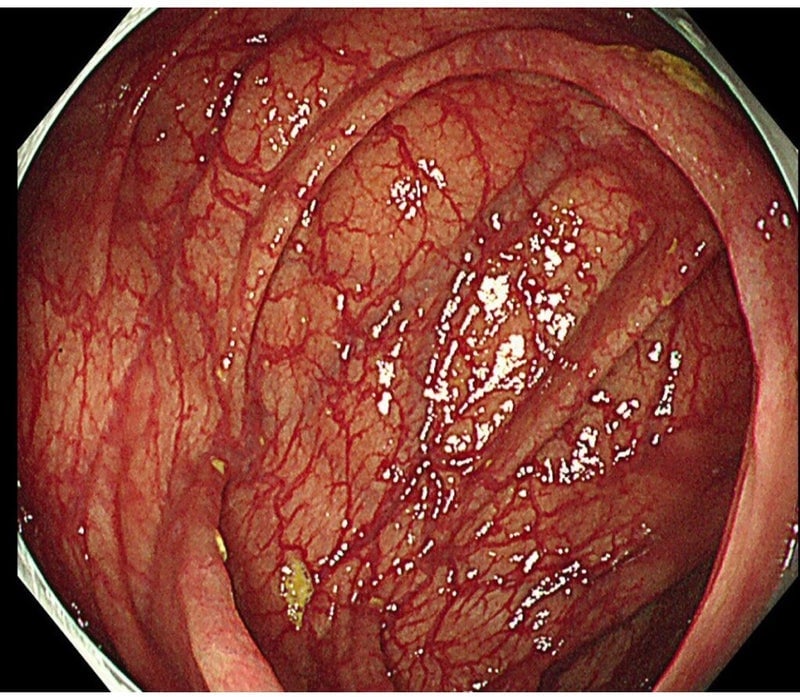

辞めて1年程で色素沈着と腸管の弛緩も改善

↓は正常になるまで2年